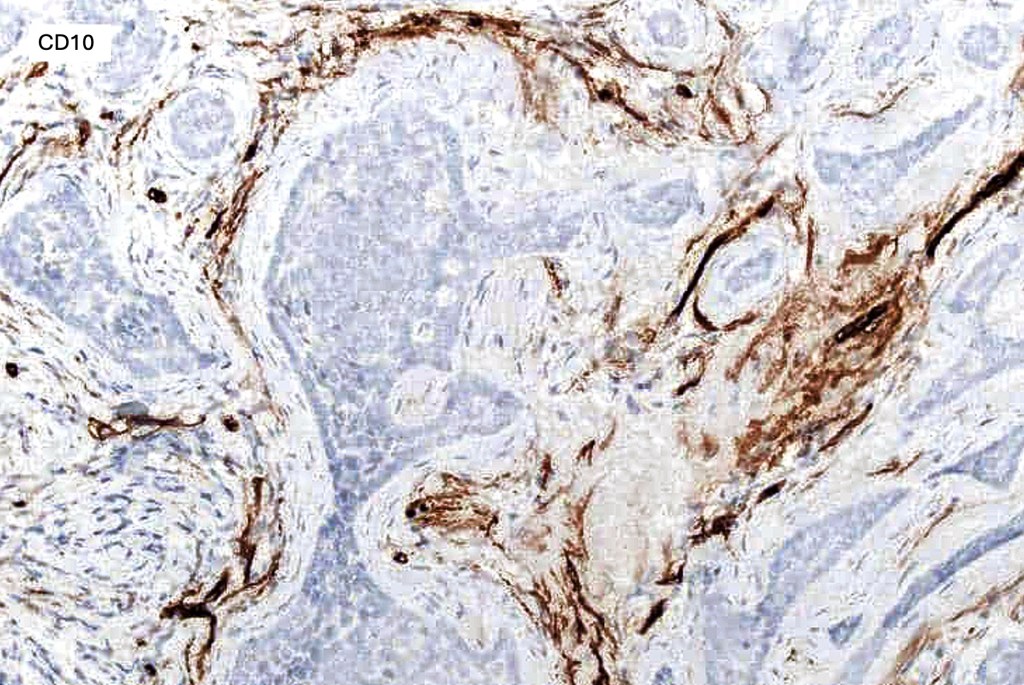

.Stromal CD10 & CD34